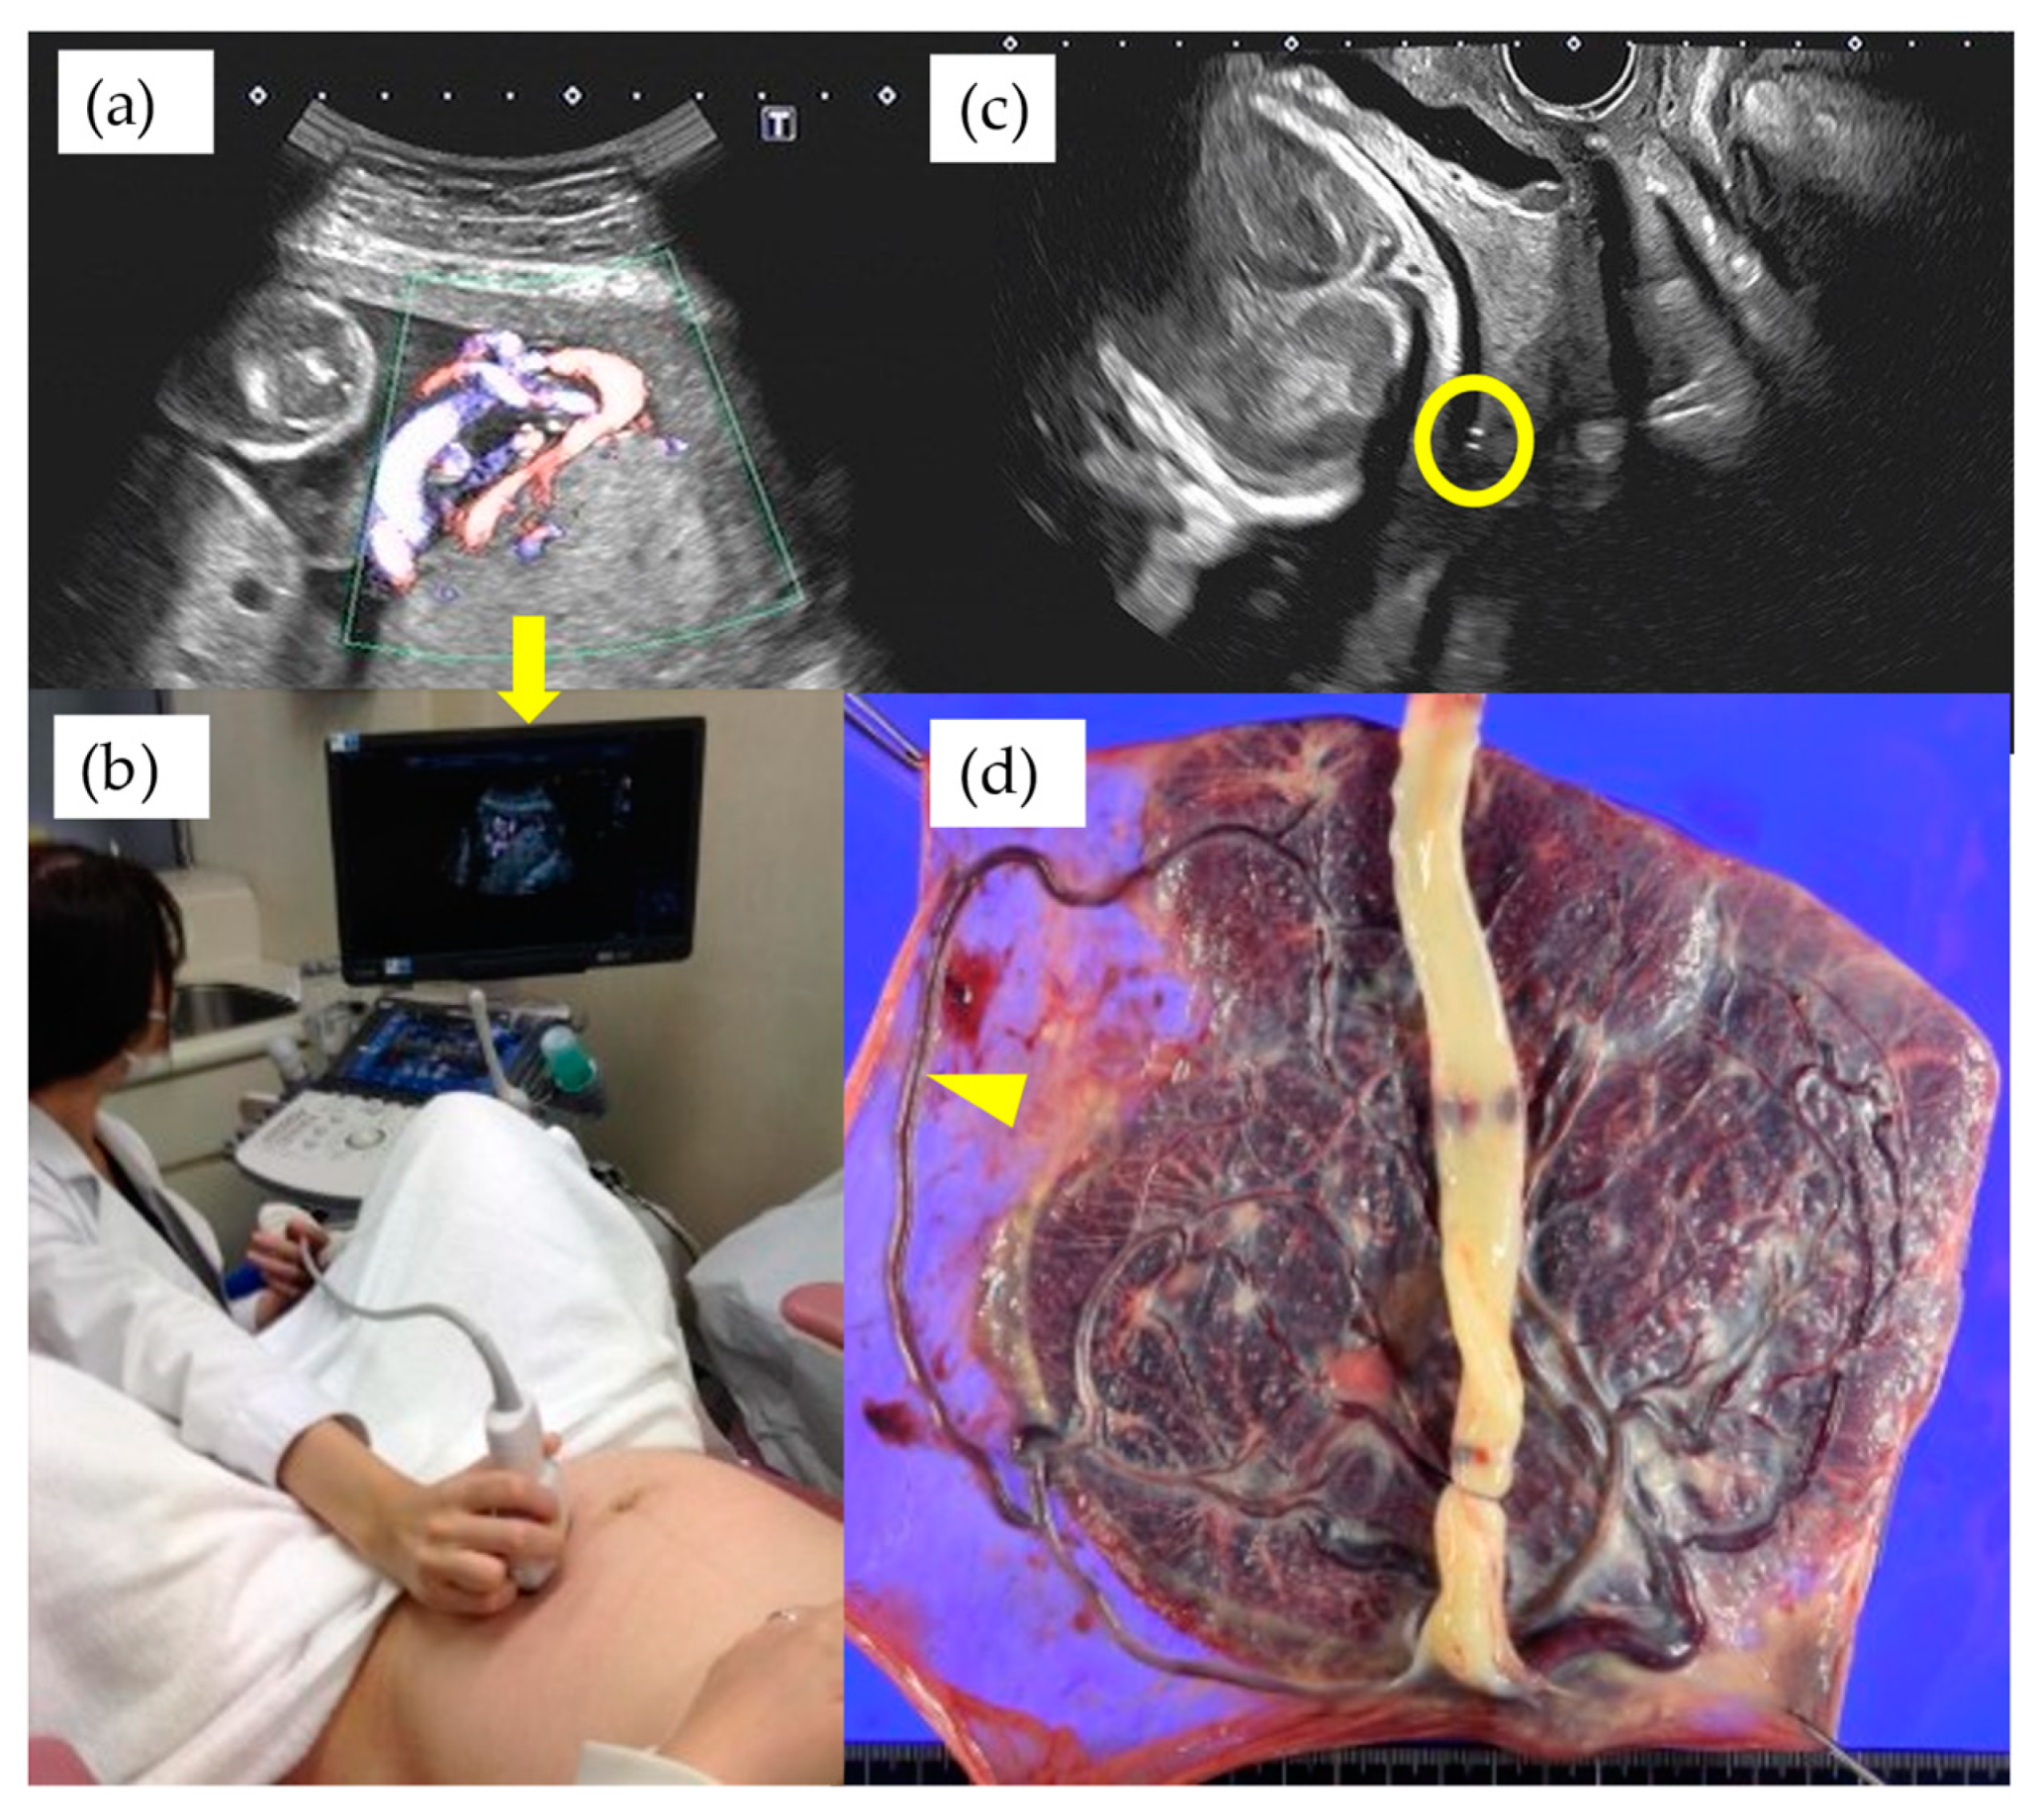

Table 3 shows the results of management and operative outcomes. In 31 cases (56.4%), including three twin pregnancies, tocolytic therapy was necessary (ritodrine hydrochloride and/or magnesium sulfate), and a steroid for fetal lung maturation was given in 9/13 cases (69.2%) delivered before the 34th GW. An abnormal fetal heart rate pattern without uterine contractions was detected in one case in the type 1 group, and this case exhibited a relatively thick artery near the internal ostium (Figure 2). Cervical cerclage via the McDonald technique was performed in two cases in the type 1 group. One of these cases was a singleton pregnancy at 20th GW and a cervical length of 2.1 cm, delivered by CS at 33rd GW. The other was a monochorionic-diamniotic pregnancy case at 20th GW and a cervical length of 1.7 cm, delivered by CS at 31st GW; this patient had a previous history of preterm singleton delivery at 34th GW. Blood flow of fetal vessels was confirmed post-cerclage in both cases (Figure 3). Resolution was observed in 12 cases (21.8%) in total. An emergent CS was performed in 25 cases with increased uterine contractions and in one case with an indication of hypertensive disorder of pregnancy; none of these cases experienced the premature rupture of membranes. Although the Ward technique was more frequently used in the non-type 1 group, the details as to operative outcome showed no significant difference between the two groups. The transection of the placenta to approach the fetus was not used in any of the cases. All cases underwent a cesarean section, even in those cases of resolution of VP.

Figure 4. A case of VP at 27th GW showed the velamentous insertion site relatively distant from internal cervical ostium shown with TA-US (a) and the hand of examiner positioned at the navel height of the patient to visualize the cord insertion (b). Yellow circle indicates the fetal vessel running on the internal cervical ostium detected by TV-US on the same day of examination (c) and arrowhead indicates the macroscopic finding of very long aberrant circumventing vessel (d). The arrow in Figure 4a indicates the magnified monitor of the ultrasound image of the Figure 4b.